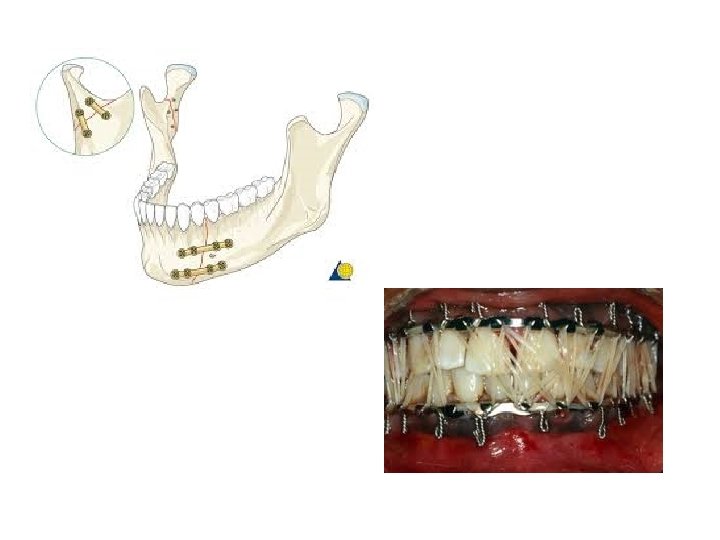

II Injuries cont 2) Face injuries from article- “In Your Face” Directions: 1) underline def, symptoms and TX as we read 2) Answer question on back of packet Read NFL stories